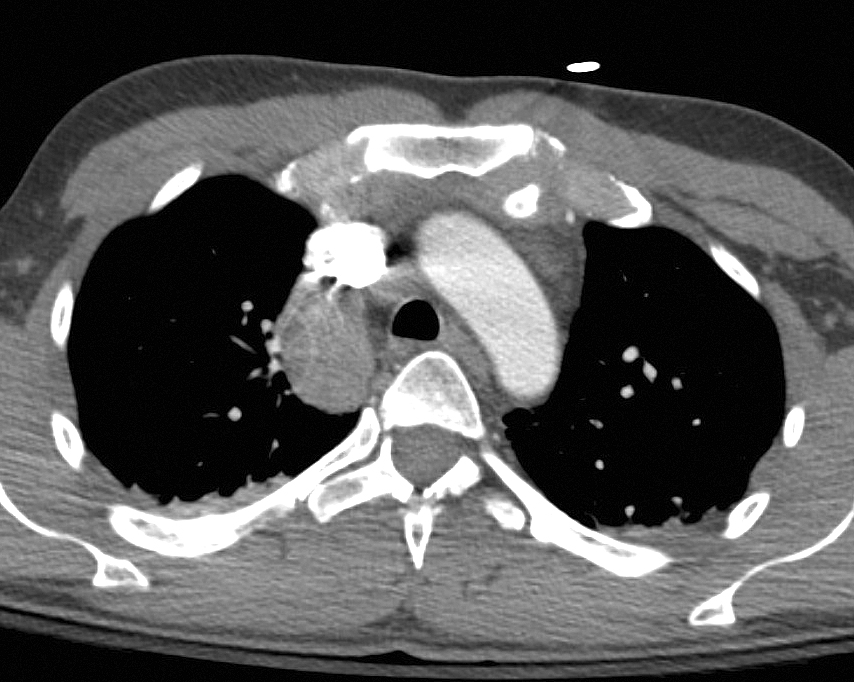

Azygous Continuation 2b